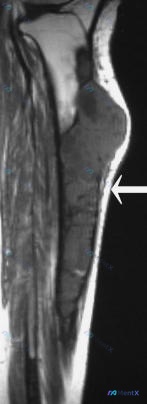

- MRI(T1 矢状位):胫骨骨干长节段占位,不均匀低信号,边界相对清晰。肿块明显突破骨皮质,向胫骨前方软组织内生长。